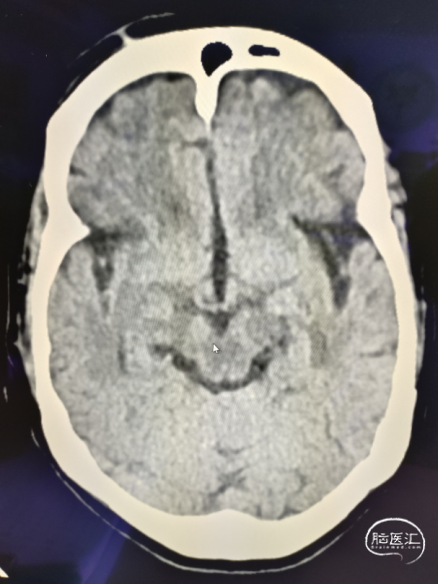

手术过程

术中

路径困难是导致困难取栓的常见原因之一,既往因为普通导引导管较硬而无法通过迂曲血管到达目标血管,并增加手术时间。同时既往中间导管通过性能差而无法顺畅的实现高到位并进行抽吸,两者大大降低了取栓效率。普微森MidAccess™导引导管 088-90 cm具有8F普通导引导管直径,通过性能明显优于普通导引导管,特别是在该病例RCCA如此迂曲的情况下,仅在泥鳅导丝引导下就可以顺利通过Z字型迂曲到达C1段,为后续068中间导管提供了有力支撑并缩短的取栓距离。普微森MidAccess™导引导管 068-132 cm具有口径大、高到位、耐疲劳的特点,在微导管微导丝引导下3次顺利通过眼动脉段并送至RMCA起始段及M1中远端进行抽吸,不仅缩短了取栓时间,也避免了反复支架取栓对血管管壁的损伤。